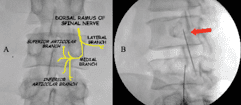

• 2. Medial Branch Blocks (MBB):

• The medial branches are small nerves that transmit pain signals from the facet joints to the brain.

• In a medial branch block, a local anesthetic is injected near these nerves to temporarily block pain signals.

• This procedure is often used as a diagnostic tool to confirm if the facet joint is the source of pain.